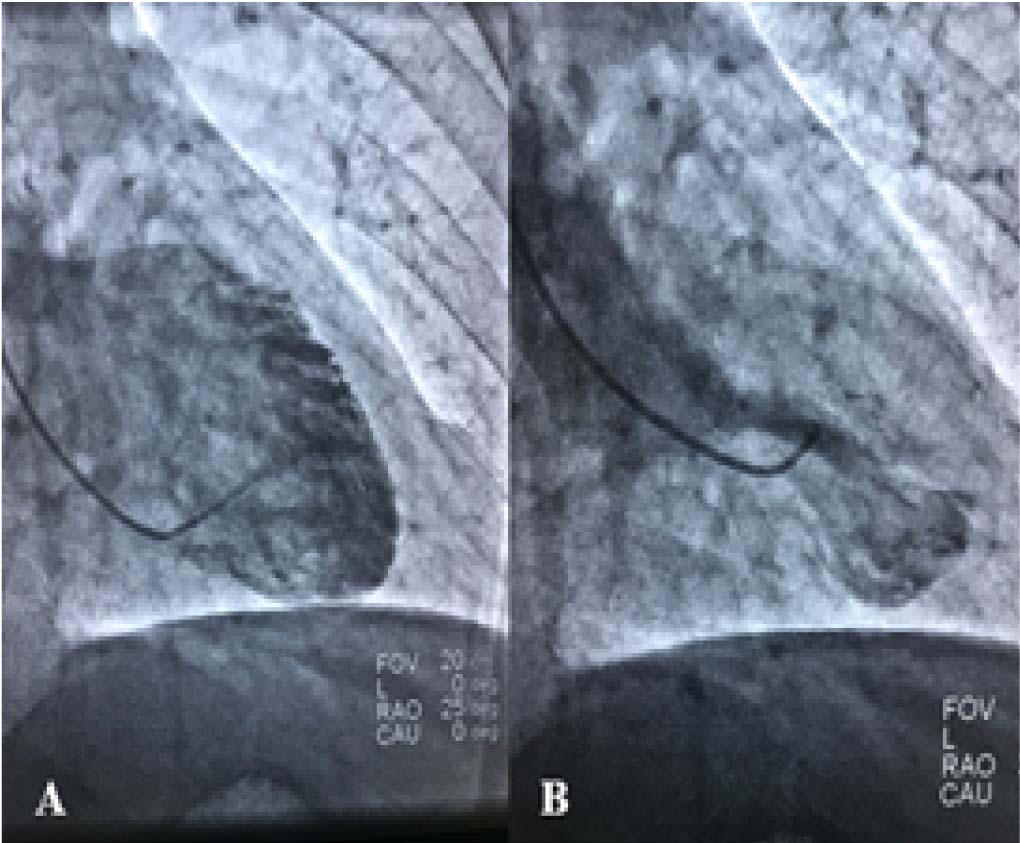

Se realizó coronariografía a las dos horas del inicio del cuadro clínico del paciente, donde no se observa obstrucción, estenosis significativa ni evidencia de ruptura aguda de placa en ninguna arteria epicárdica, incidentalmente se evidencia estenosis del 60% en origen de una rama diagonal de tamaño mediano con flujo distal conservado ( Figura 2); en el ventriculograma se evidenció discinesia apical e hipercinesia basal ( Figura 3).

En el caso presentado, se esperaba encontrar obstrucción de la arteria coronaria derecha ó menos probable, la arteria circunfleja, sin embargo las mismas se encontraban sin lesiones angiográficas, por lo que se efectuó ventriculografía donde se observó discinesia apical e hipercinesia basal 3, 4. Fue de esta manera que con el antecedente de estrés emocional y las alteraciones electrocardiográficas se planteó el diagnóstico de Miocardiopatía por estrés o Síndrome de Takotsubo cumpliendo los criterios de la Clínica Mayo 5- 9.